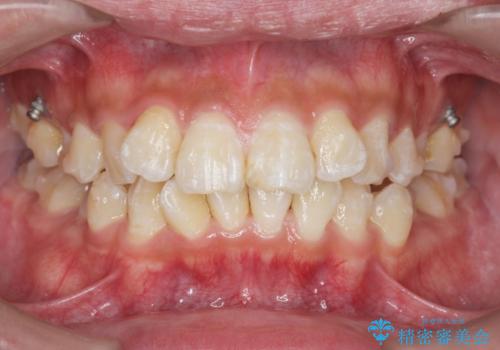

遠心移動を伴うマウスピース非抜歯矯正治療

- 「前歯の見た目を改善したい。」と矯正治療を希望され来院されました。

前歯のガタつきに加え、上顎が前にある咬合関係(上顎前突)を改善すべく、マイクロインプラントを用いた上顎奥歯の後方移動、拡大、ディスキングを用いたマウスピース矯正治療を計画します。

マイクロインプラントを使用したことで、しっかりと遠心移動が為され、良好な咬合関係が達成されました。